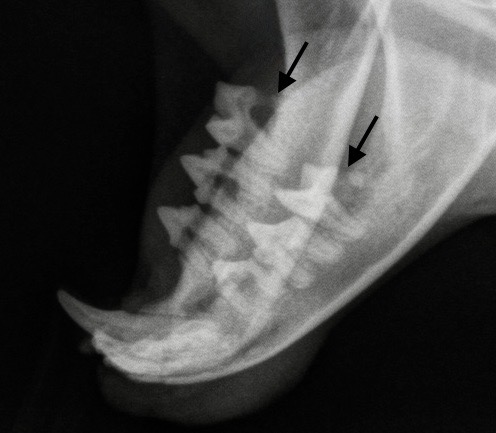

La photo de gauche montre des lésions de résorption du collet, sur une prémolaire et une molaire inférieures d’un chat en cours de détartrage : les flèches montrent la distance importante qui sépare la gencive (qui saigne au moindre contact), de la couronne de la dent : cette dernière est lysée, notamment sur la partie la plus caudale de la molaire. Photo de droite : et voilà ce que ça donne à la radio : la racine caudale des deux molaires inférieures a été rongée au point de quasiment disparaître (flèches).

On va le voir juste après, la mesure la plus importante dans le traitement de la GSCF, ce sont les extractions dentaires – et souvent, ce sont presque toutes les dents que l’on retire. Et on a vu plus haut qu’un débris de racine qui traîne alors que le reste de la dent est parti, peut suffire à entretenir l’inflammation de la bouche. Il est donc intéressant de pratiquer des radiographies dentaires avant de s’attaquer aux extractions, afin de débusquer les racines enfouies qui pourraient passer inaperçues après un simple examen externe. (Photo ci-contre : la racine postérieure de ces deux molaires ne va pas tarder à casser, avec le risque que l’extrémité arrive à se faire oublier, bien cachée au fond de son alvéole !)